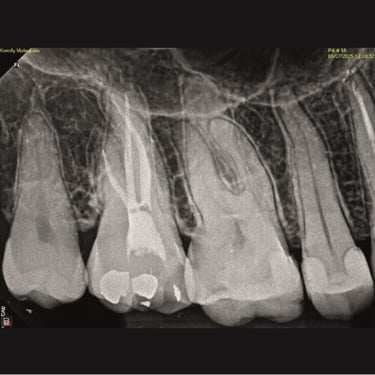

CASOS CLÍNICOS ENDO

Abaixo você encontra fotos de alguns dos tratamentos realizados.